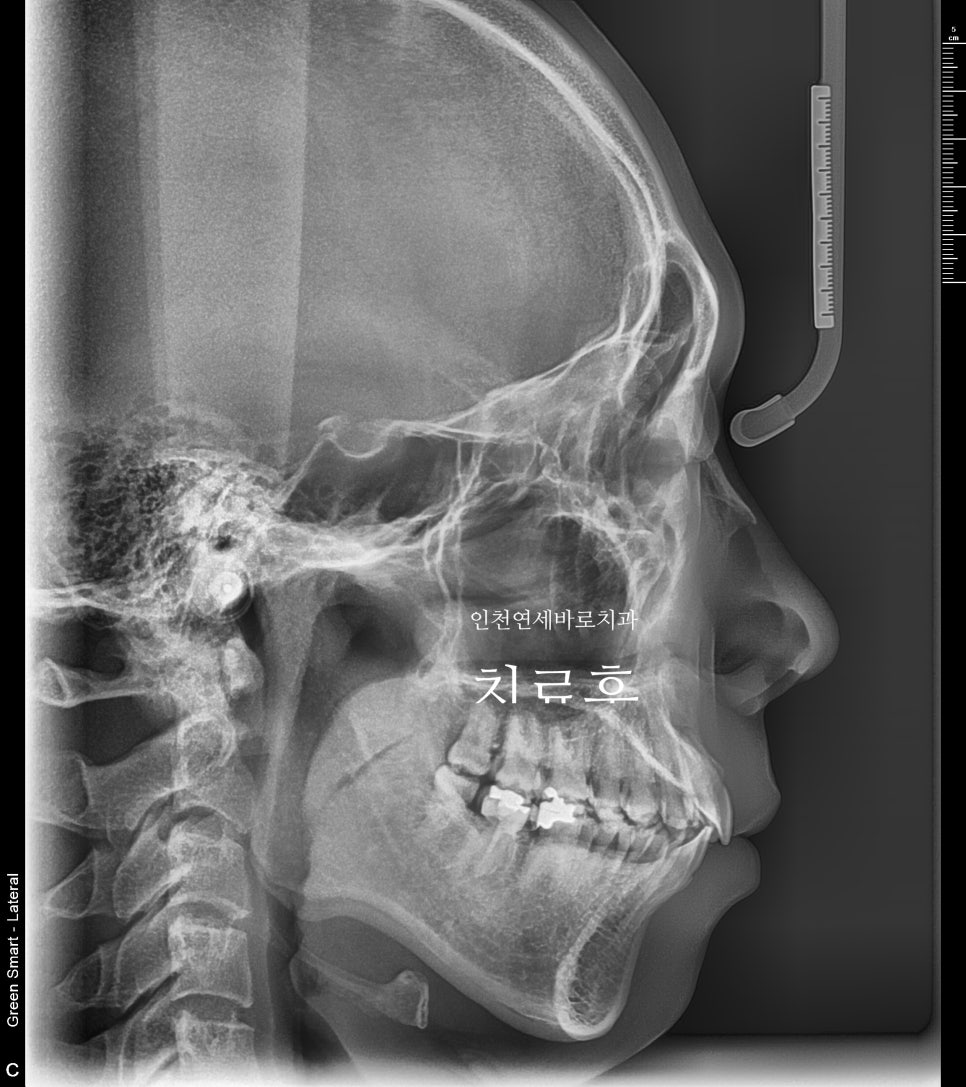

치료전과 후의 엑스레이 입니다.

악궁의 확장을 통한 앞니의 후방이동도 최대한 이루어냈습니다.